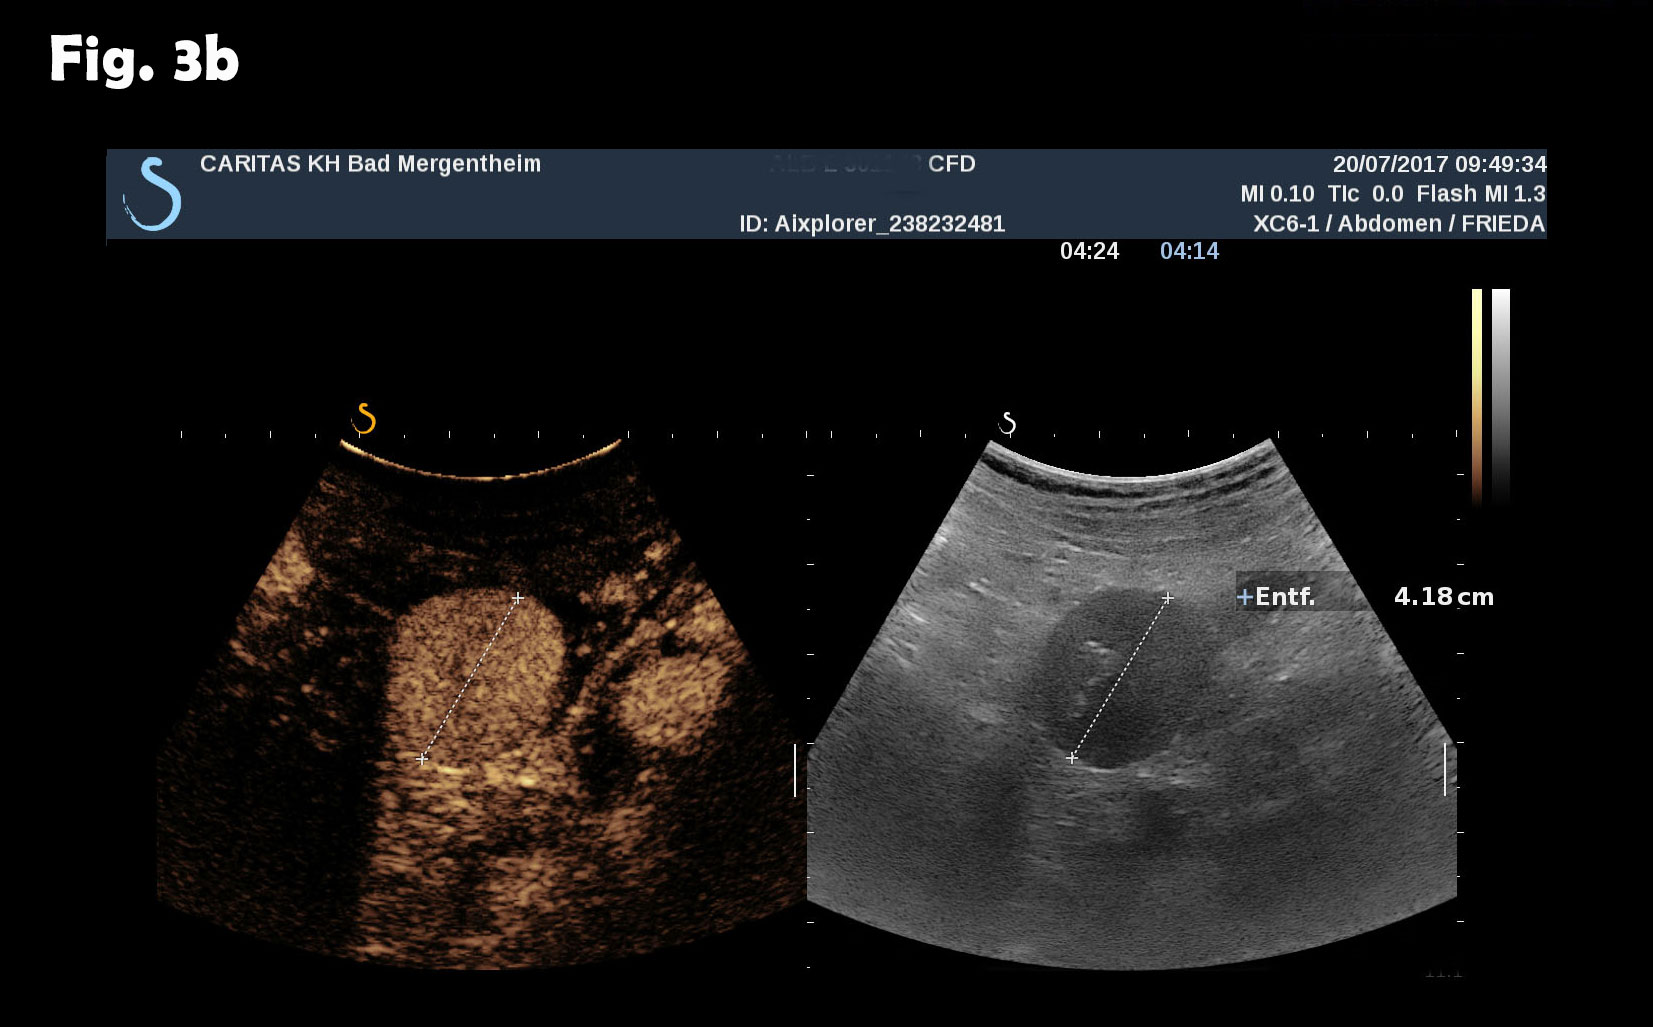

Computed tomography of the chest revealed pneumonic infiltration but was otherwise normal. The endoscopic examination of the upper and lower gastrointestinal tract was normal. Contrast enhanced ultrasound (CEUS) showed arterial and late phase enhancement lasting more than 5 minutes in all examined nodules. After Biopsy the ultrasound examination was performed showing multiple almost echofree but also echogenic round and oval shaped focal peritoneal masses with a size of up to 46 mm [Figure 2-4].

Figure 3: The same lesion as shown in Figure 2. Contrast enhanced ultrasound revealed arterial (a) and late phase enhancement lasting > 4 minutes (b).

Figure 4: At different abdominal locations more echogenic round oval lesions upt to 30 mm were identified by ultrasound. The lesions were best depicted during the late phase enhancement behind the accessory spleen next to the lesion shown in figure 2 (a) and elsewhere in the abdomen (b). The Figure 3c represents the CT finding shown in figure 1.